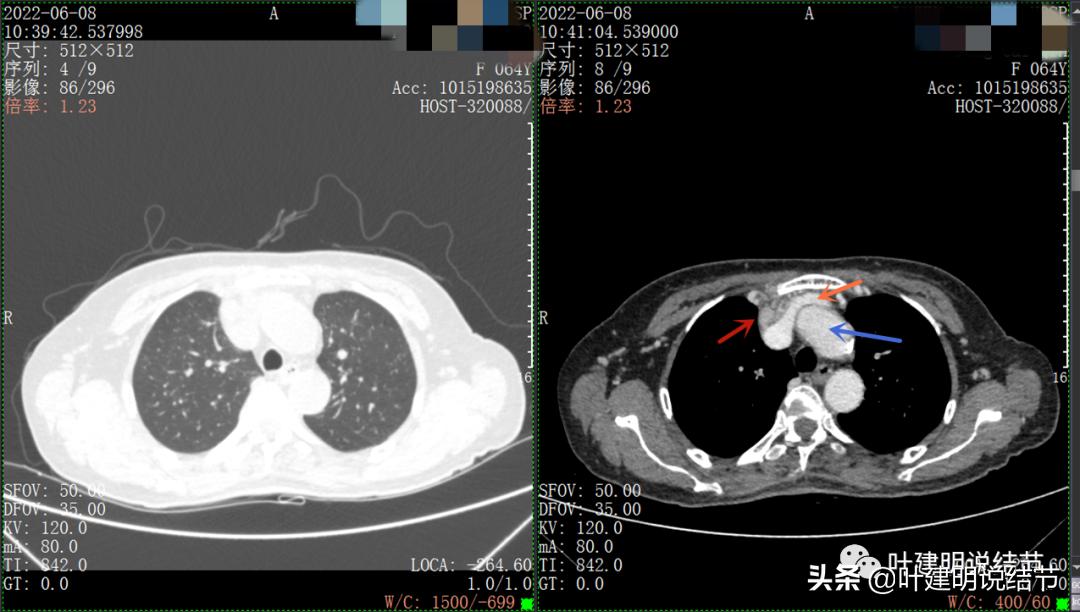

以下图片左侧是肺窗,右侧是纵隔窗。红色箭头示病灶,桔色箭头示无名静脉,黄色箭头示支气管,砖色箭头示上腔静脉,蓝色箭头示主动脉,紫色箭头示肺动脉。

病灶最大横断面水平,在冠状位上显示病灶多个中心似的,从上到下纵隔都有

病灶之间似不相连的,矢状位上见从上到下延续的

病灶占据前纵隔从上到下全程,多中心,密度不均,对心脏与大血管有压迫,没有明显侵犯

病灶表面不平,中间有坏死

上图示最大横断位达5厘米